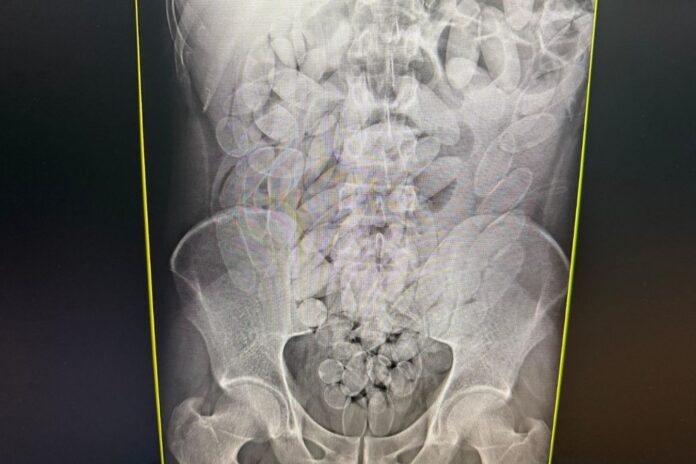

Os passageiros, sete homens e uma mulher, foram levados à Santa Casa de Corumbá, onde exames de imagem confirmaram que haviam ingerido cápsulas com substância parecida com pasta base de cocaína.

As cápsulas foram retiradas por meio de procedimento médico. Os suspeitos foram encaminhados à Polícia Federal e permanecem à disposição da Justiça.